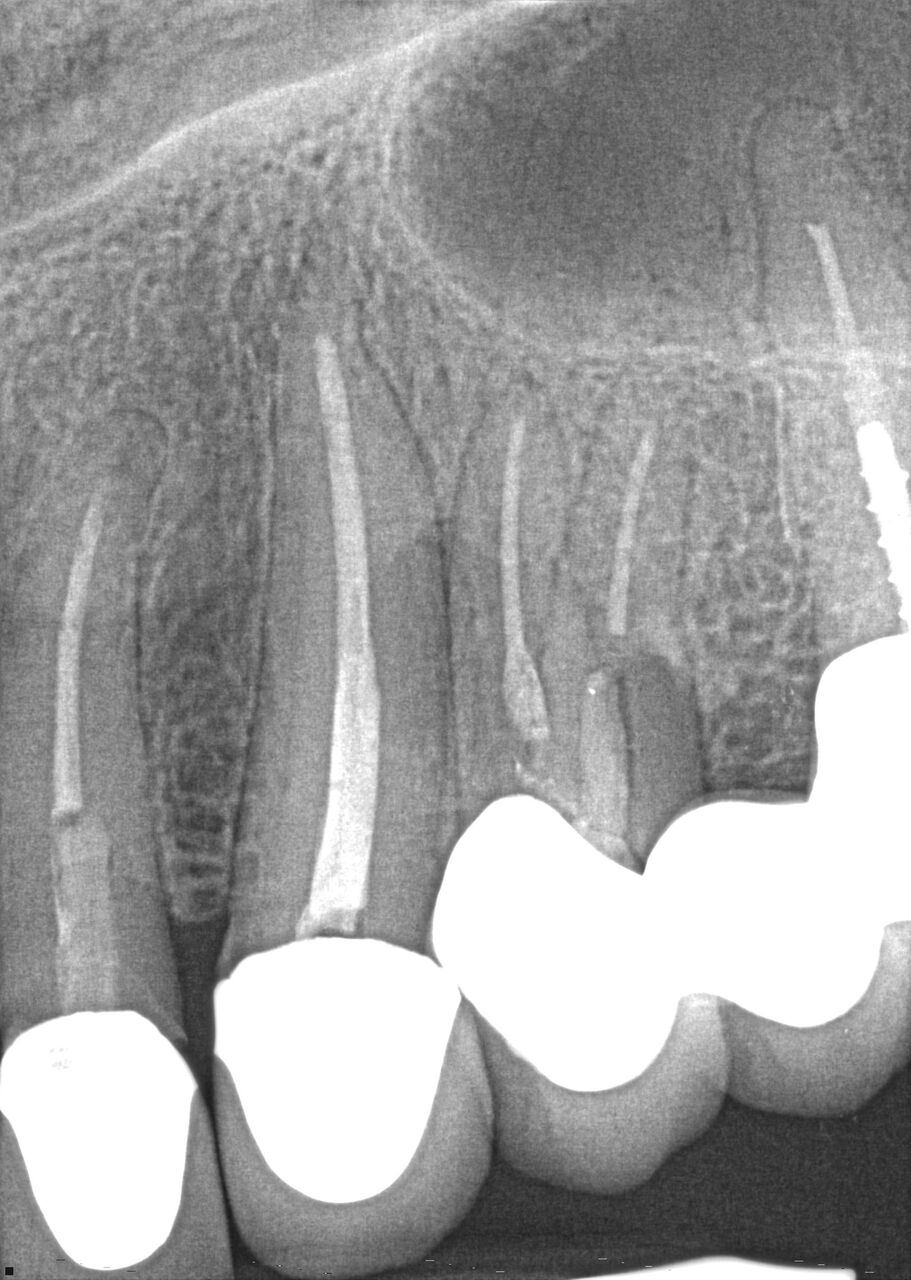

(4.) Radiograph showing immediate implant of No. 19 with immediate restoration day of surgery.

Figure 4

A 63-year-old woman presented with severe pain on biting of tooth No. 19 (Figure 1). Clinically there was pain on percussion and significant periodontal probing along the mesial root. The patient was anesthetized with infiltration anesthesia and the crown was horizontally sectioned from the lingual of the tooth. The remaining tooth was sectioned so the roots could be extracted individually. The socket was fully debrided and an implant was placed (Figure 2), which was prosthetically correct and stabilized in excess of 45 Ncm. The bone was milled to allow for unimpeded placement of a temporization abutment. The initial crown was revised to be the temporary crown in infraocclusion. Cement was extruded extraorally (Figure 3) prior to seating of the temporary restoration. The socket was sealed with the temporary crown and there were no sutures or bone graft (Figure 4 and Figure 5).